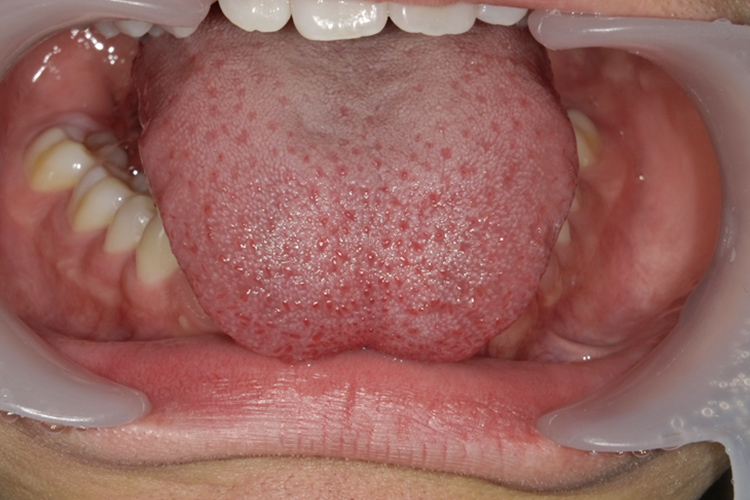

舌小帯手術

舌小帯とは、舌の裏側にある下顎と舌をつなげている筋のことをいいます。

舌小帯が短いと舌を動かしにくく発音しにくいなどの症状が出てしまい、滑舌や歯並びにも関わってくる場合があります。

舌小帯は舌の前方まで付着した状態になっているため、あっかんべーをしたときに舌の先端がハート形になって引っ張られてしまったり、サ行が発音しにくかったりなどの症状もあります。

症状の改善には舌小帯切除の手術が行われますが、当院では炭酸ガスレーザーを用いた切除方法で治療を行っています。レーザー治療では縫合の必要がなく、痛みを抑えることができます。